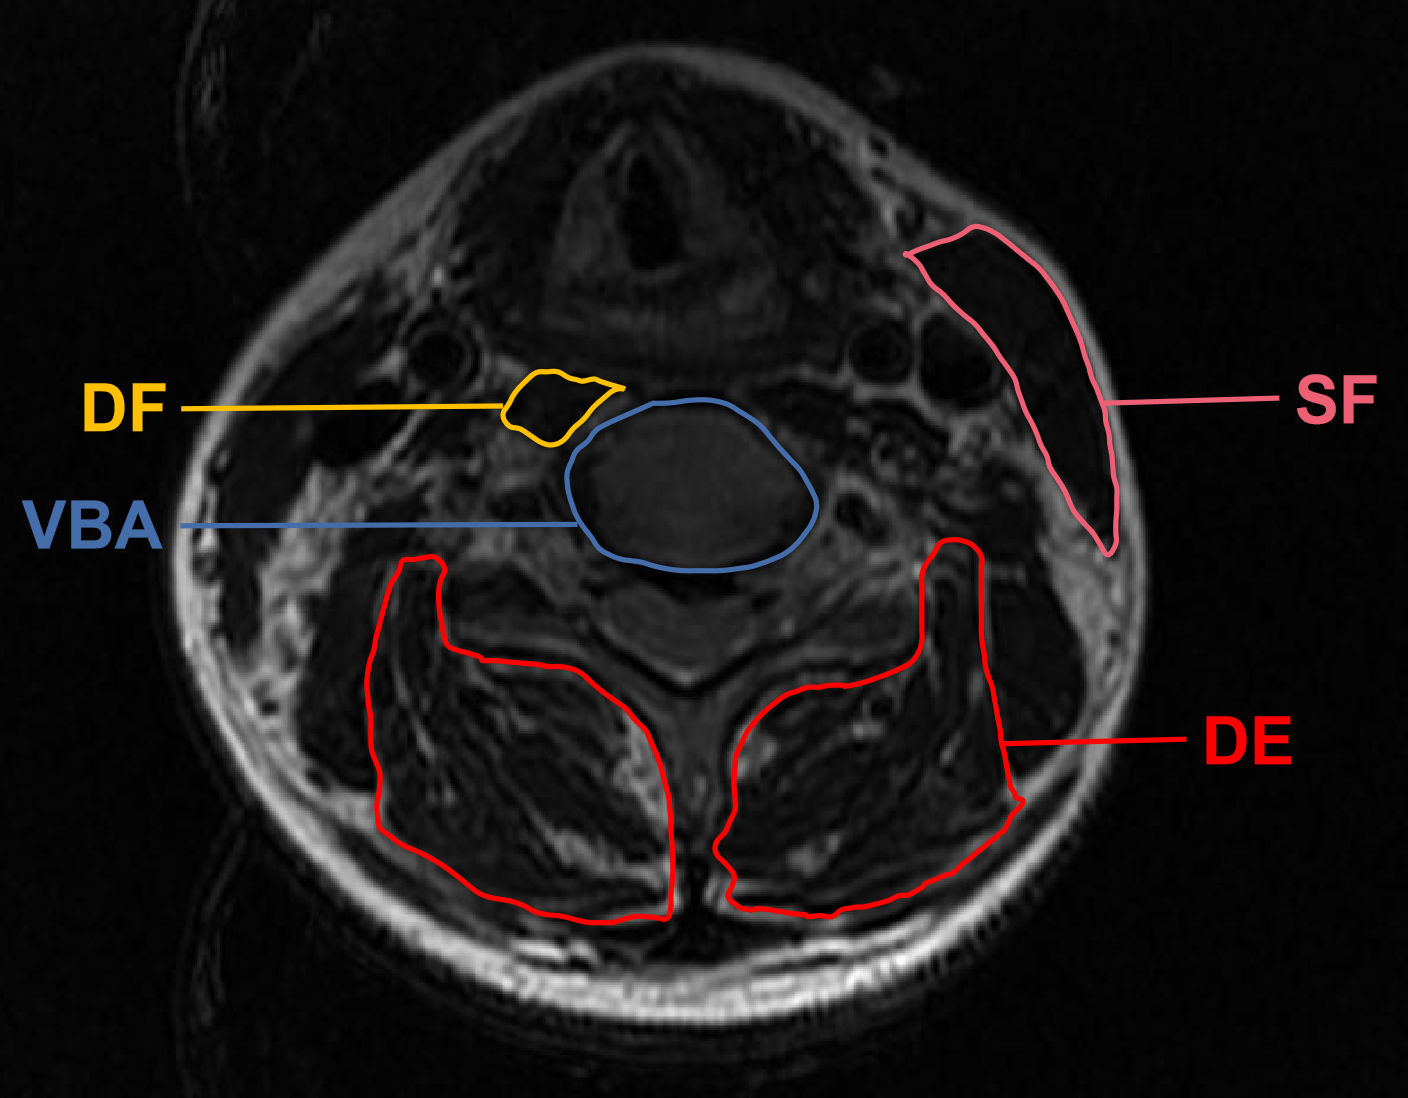

In addition, CSA measurement method was based on a technique standardized by Takayama et al. (4). The measured flexors included sternocleidomastoid (superficial flexor, SF) and longus colli (deep flexor, DF). The extensors included multifidus and erector spinae (deep extensor, DE). CSA was defined by manually tracing the fascial boundary of CPM bilaterally. Moreover, vertebral body area (VBA) was introduced to eliminate biases arising out of variations in physiques (Figure 3) (17). The image-processing software platform (Image J, National Institutes of Health, Bethesda, MD) utilized enabled us to outline and analyze the regions of interest of CPM and VBA with a graphic cursor. The final FI classification and morphometry data were averaged between bilateral paraspinal muscles.

Figure 3

Demonstrative axial T2 magnetic resonance imaging sections of the regions of interest applied in measuring the cross-sectional area. SF, superficial flexor; DF, deep flexor; DE, deep extensor; VBA, vertebral body area.